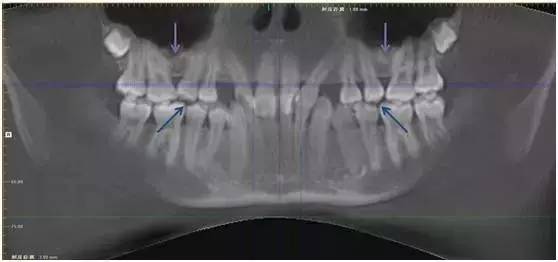

因此患者接受了上颌窦底提升植骨术,一年后牙槽基骨成骨充分,牙齿自行正位萌出。此时再进行正畸治疗,难度和风险将大大减小。

图:上颌窦底提升植骨术后一年